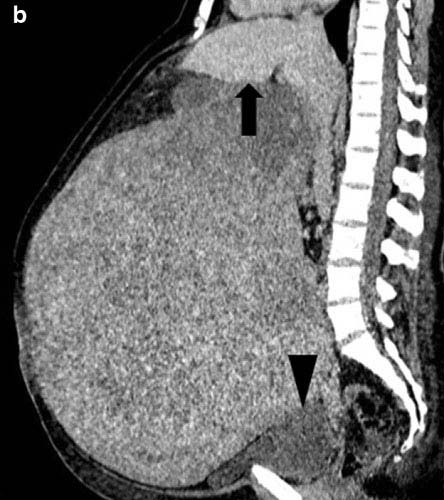

거대 자궁근종으로 뱃속이 가득 차있는 독일 여성의 CT 사진./사진=의학사례보고저널

독일 UKSH(Universitatsklinikum Schleswig-Holstein) 대학병원 의료진은 46세 독일 여성 A씨가 15년간 자궁 출혈이 계속되고 복부가 점점 커지는 증상이 지속됐다며 산부인과를 찾았다고 밝혔다. 한 달에 생리를 여러 번 하고, 한 번 생리할 때 출혈량이 과다한 문제도 있었다. 전에도 병원을 몇 번 방문했지만, 당시 영상 촬영 등 철저한 검사를 하지 않아 종양이 발견되지 않았다. 하지만 UKSH 대학병원 의료진 진찰 결과, 복부가 과도하게 확대되고 늘어져 있었으며 양쪽 옆구리가 무언가로 가득차 있는 게 확인됐다. CT 촬영을 했더니, 거대한 크기의 종양이 발견됐다. 의료진은 수술로 종양을 제거했고, 종양 크기를 측정한 결과 부피가 무려 52cm x 37xm x 34cm에 달했고, 무게는 16.4kg이었다. 전체는 양성이 자궁근종이었으며 암은 아니었다. 다행히 A씨는 수술로 종양을 제거하고 입원 5일 만에 합병증 없이 퇴원했다.